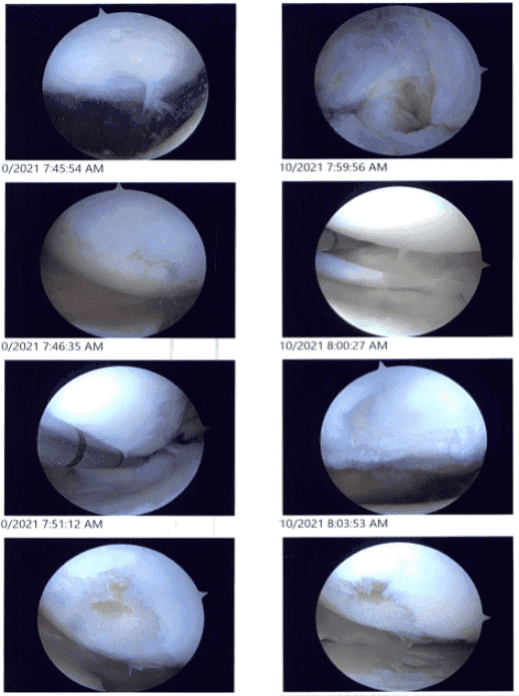

Intraoperative images

Examination of the patellofemoral joint showed a grade I to grade II patellofemoral arthritis. Examination of the medial compartment showed a medial meniscus tear near the root. A medical entry portal was made with the use of a spinal needle. The probe was inserted to further examine.

The medial meniscus root was found to be intact. The shaver was used to shave the root with the use of a straight biter and bitters to do a meniscectomy of the medial meniscus.

The osteochondral lesion of the medial femoral condyle was debrided with the use of a shaver. The abrasion chondroplasty was performed over the medial femoral condyle.

Examination of the intercondylar notch showed a degenerative ACL, but the ACL was intact. Examination of the lateral femoral condyle showed a radial margin degenerative tear of the lateral meniscus, which was removed with the use of a shaver.

Examination of the patellofemoral compartment showed an osteochondral lesion, which was debrided with the use of a shaver. Final pictures were taken and saved. The knee was thoroughly irrigated and drained.